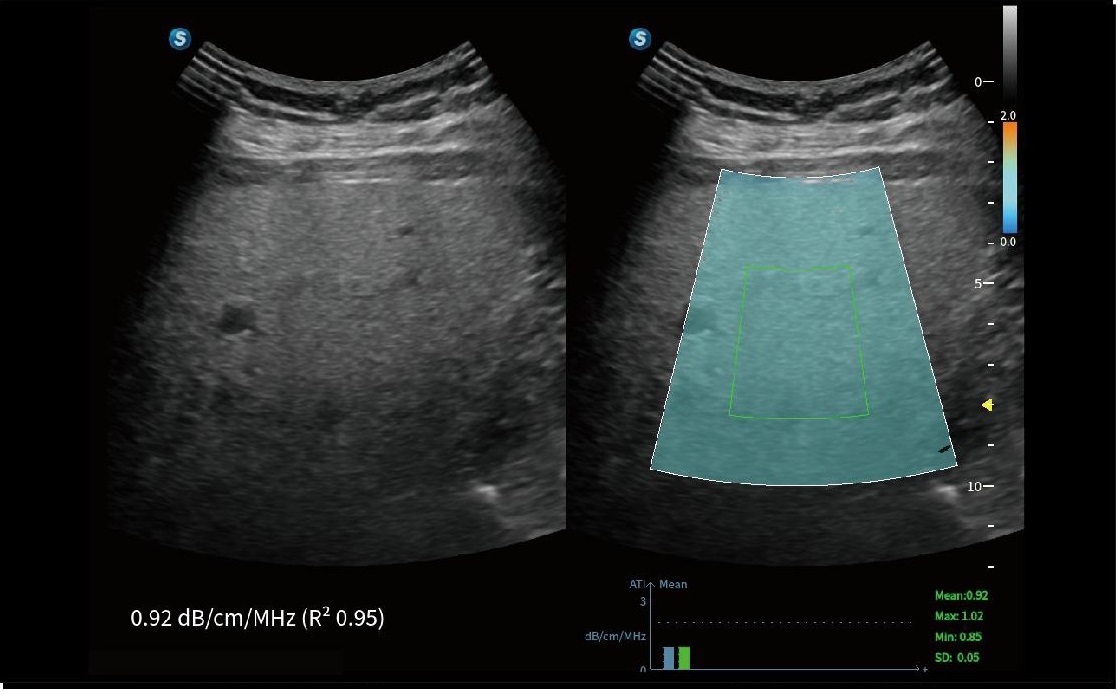

ATI

ATI (Akustik Zayıflama Görüntüleme), zayıflama katsayısını ölçerek karaciğer steatozunun nicel değerlendirilmesini sağlar ve klinisyenlerin steatoz derecesini değerlendirerek güvenilir bir prognostik tahmin yapmalarına yardımcı olur.